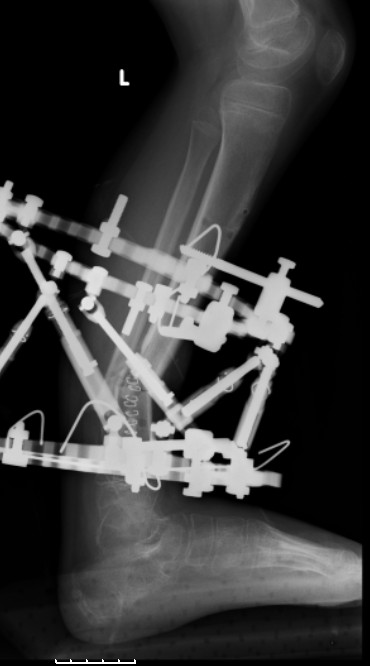

5. Ну и чтобы не быть голословным. Молодой человек подорвался на фугасе (Чечня, 2005 год). Свежие рентгенограммы:

Соответственно ожоги и дефект мягких тканей, переломы костей стопы и пр. Наложили аппарат

Илизарова (как придется), хирургически обработали и героически заживляли мягкие ткани с многочисленными кожными пластиками. В итоге через полгода я принял его вот таким:

Реализовал описанную выше методику, и в итоге вот что получилось. Высылаю лишь прямые проекции,

в боковых тоже всё в тему.

Очень пригодились карбоновые кольца (Джолдас -огромное спасибо, я твой должник!!!), поскольку остеопороз дистального отломка был просто невероятный. На цифровом рентгене с трудом угадывались контуры.

Рентген в процессе перемещения - внизу карбоновые кольца, тракция фрагмента спицами с упором.

внешний вид в аппарате - не завершающем этапе, сначала стопа тоже была фиксирована в аппарате.

Сейчас аппарат сняли, но случай ещё не завершенный.

Признаюсь честно, не совсем уверен в прочности консолидации на стыке косточек. Кроме того, укорочение в районе 6 см. Сейчас реабилитация - ходит опираясь на ногу с одним костылем.

Продолжение, видимо, будет... Возможно, будем удлинять.